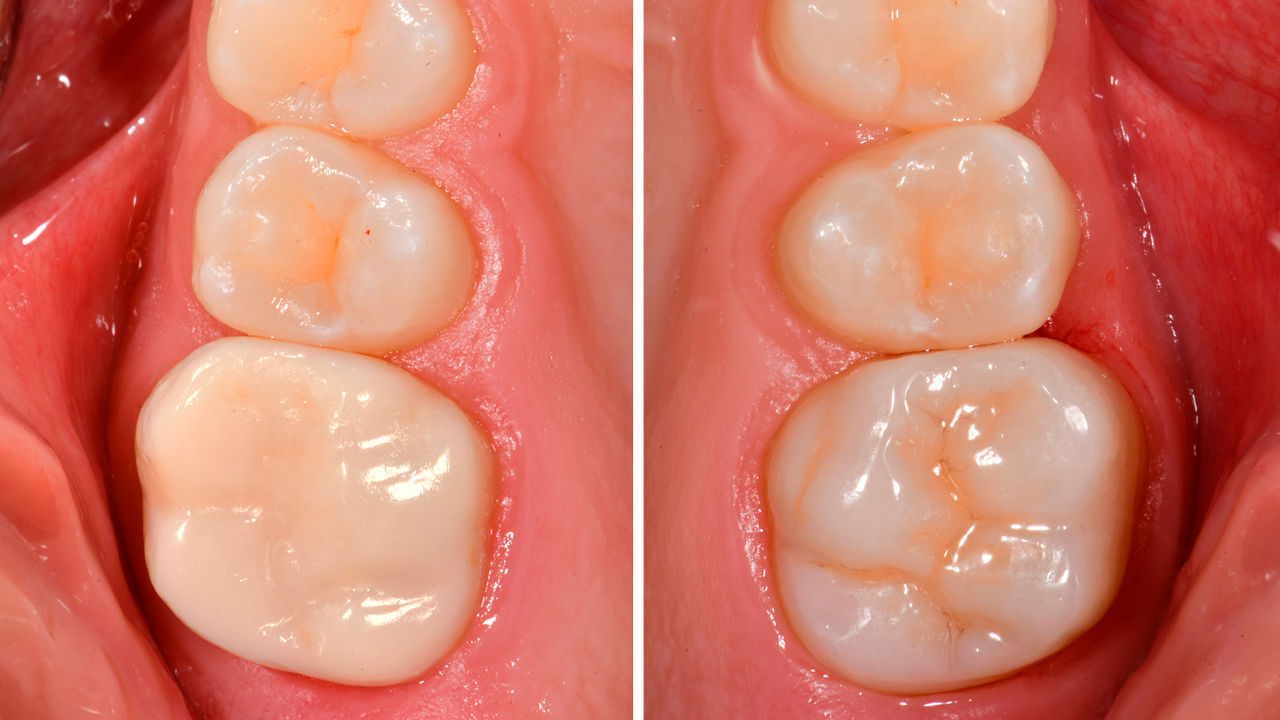

Before: Pre-operative clinical scenario after endodontic therapy.

After: 1 month after the CEREC Tessera onlay was bonded.